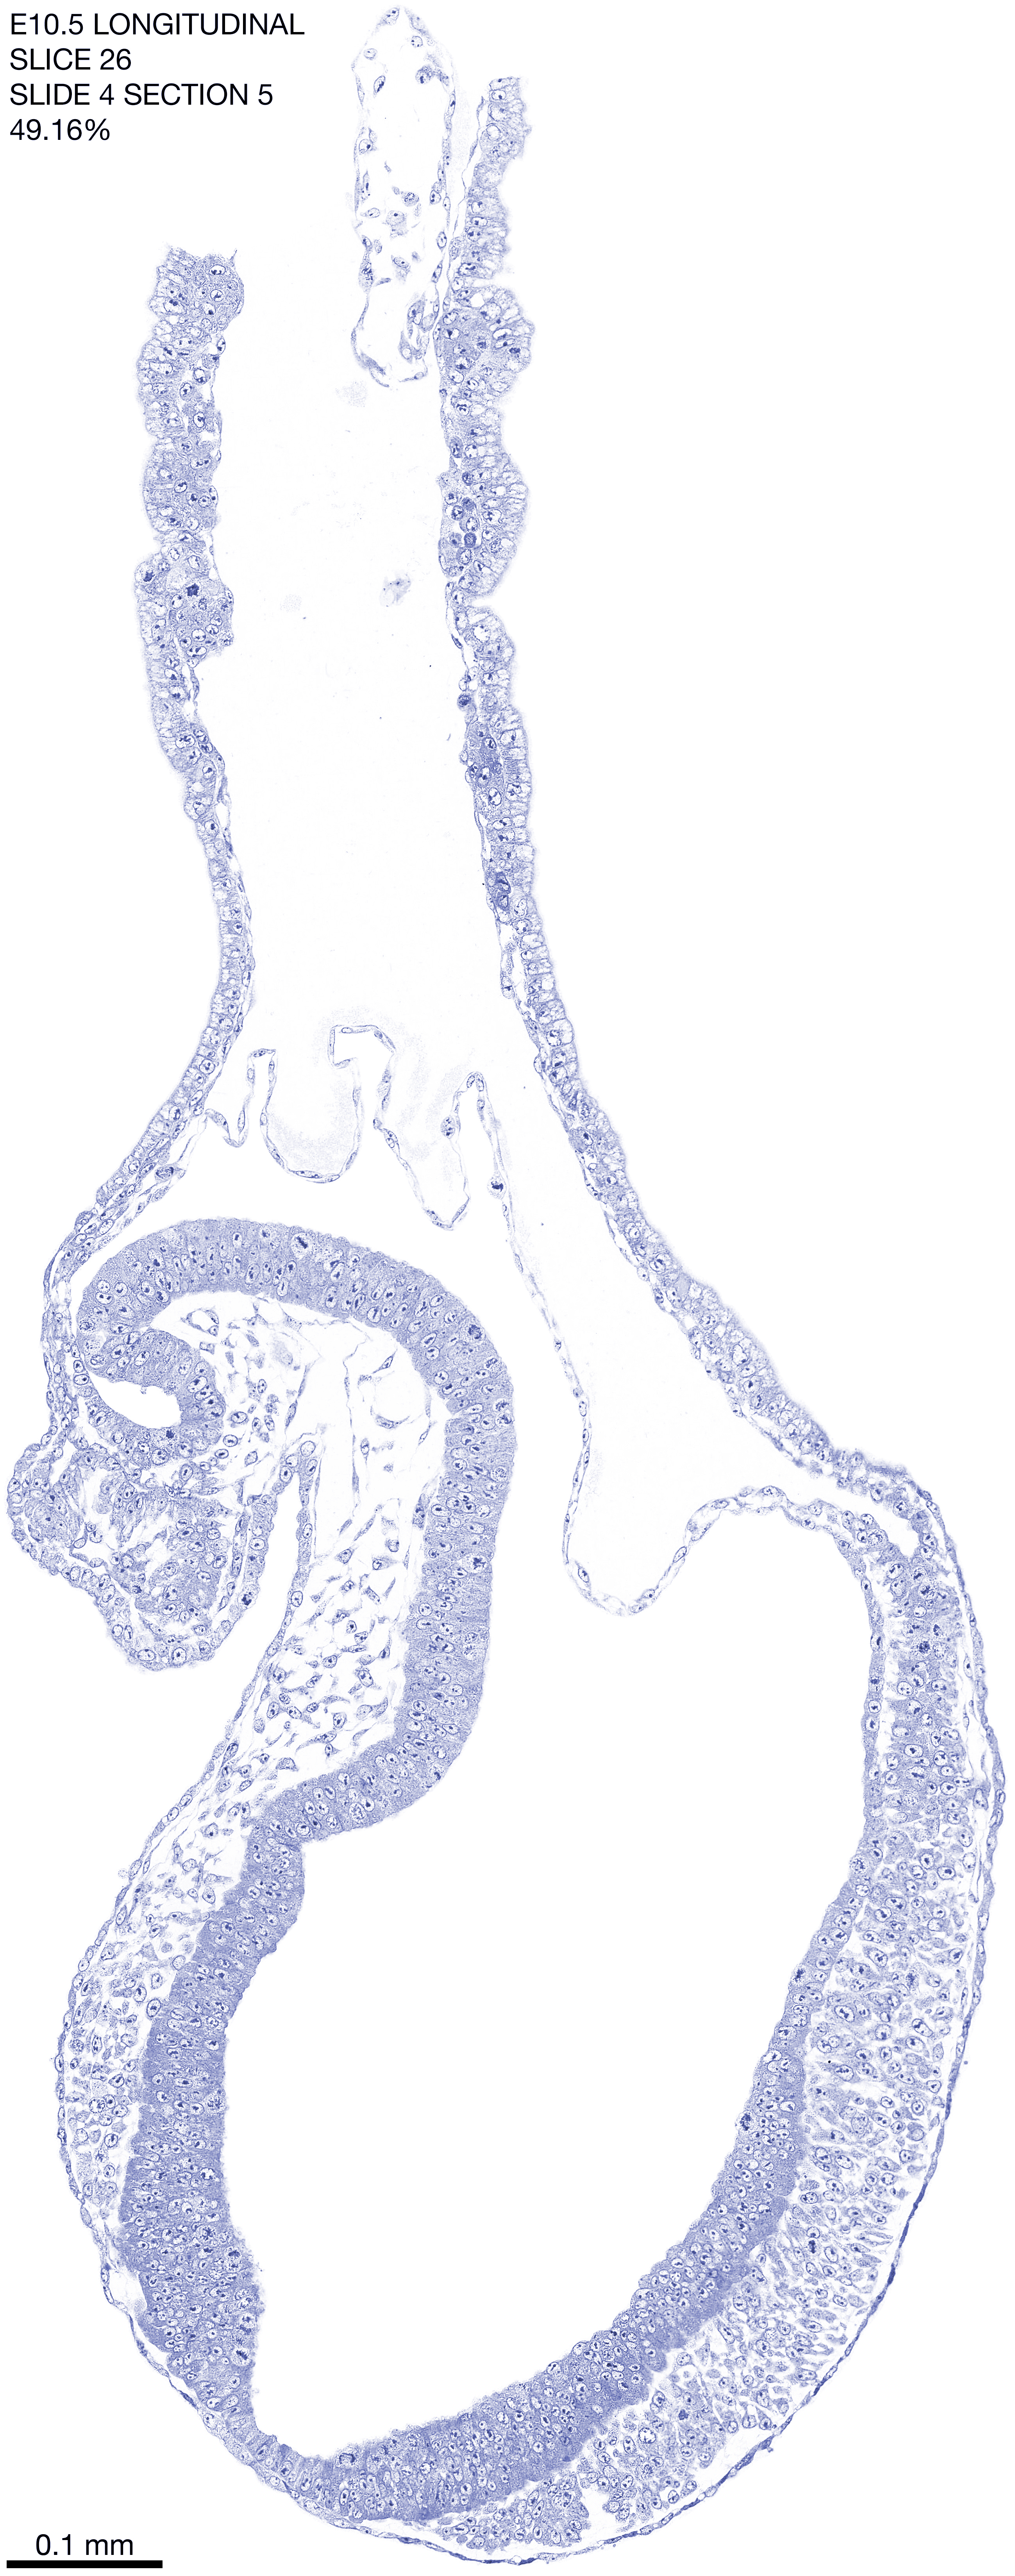

E10.5 Longitudianal Archive This page contains jpg files of ALL SLICES (each 3µm thick) that were scanned of the E10.5 longitudinally cut specimen. Download: Large | High Res Download: Large | High Res Download: Large | High Res Download: Large | High Res Download: Large | High Res Download: Large | High Res Download: Large | High Res Download: Large | High Res Download: Large | High Res Download: Large | High Res Download: Large | High Res Download: Large | High Res Download: Large | High Res Download: Large | High Res Download: Large | High Res Download: Large | High Res Download: Large | High Res Download: Large | High Res Download: Large | High Res Download: Large | High Res Download: Large | High Res Download: Large | High Res Download: Large | High Res Download: Large | High Res Download: Large | High Res Download: Large | High Res Download: Large | High Res Download: Large | High Res Download: Large | High Res Download: Large | High Res Download: Large | High Res Download: Large | High Res Download: Large | High Res Download: Large | High Res Download: Large | High Res Download: Large | High Res Download: Large | High Res Download: Large | High Res Download: Large | High Res Download: Large | High Res Download: Large | High Res Download: Large | High Res Download: Large | High Res Download: Large | High Res Download: Large | High Res Download: Large | High Res Download: Large | High Res Download: Large | High Res Download: Large | High Res Download: Large | High Res Download: Large | High Res Download: Large | High Res Download: Large | High Res Download: Large | High Res Download: Large | High Res Download: Large | High Res Download: Large | High Res Download: Large | High Res